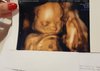

Załączniki

• 20181017_195251.jpg

20181017_195251.jpg

1,3 MB · Wyświetleń: 114